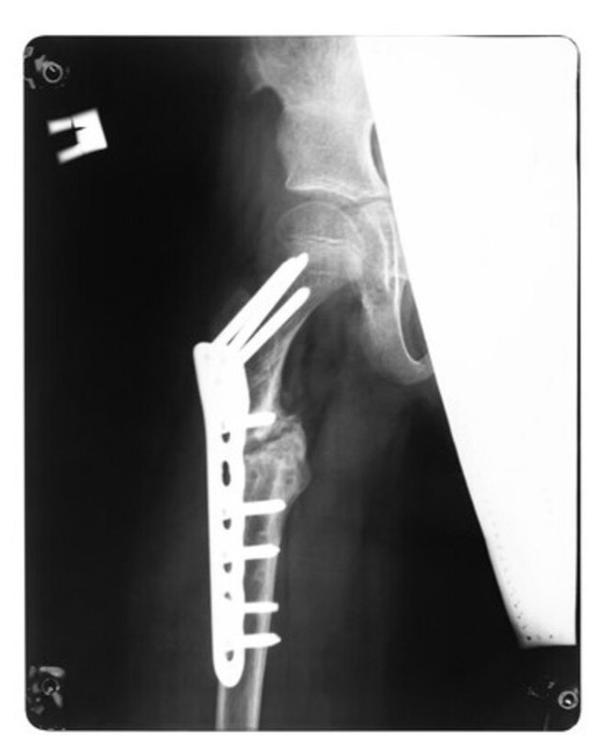

Limb Salvage Surgery In Mumbai – Saving Limbs With Advanced Surgical Care

Megaprosthesis Surgery in Mumbai – Restoring Mobility After Bone Loss

Limb Salvage Surgery in Mumbai – Preserving Mobili...